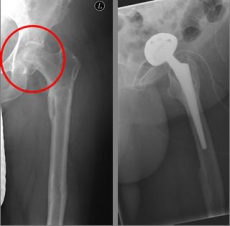

Picture: In this case, there was already a wear of the hip joint and the affected patient was relatively young, so that a cement-free total endoprosthesis (TEP) of the hip was selected for the treatment of the femoral neck fracture. Here, in addition to the femoral head, the acetabular cup was replaced by an implant.

In older age and with stronger displacement of the fracture can be done by a duo-head prosthesis. Here only the femoral head is replaced, the hip socket is preserved. In case of simultaneous hip arthrosis, a total endoprosthesis (hip replacement) with replacement of the acetabular cup can be used.